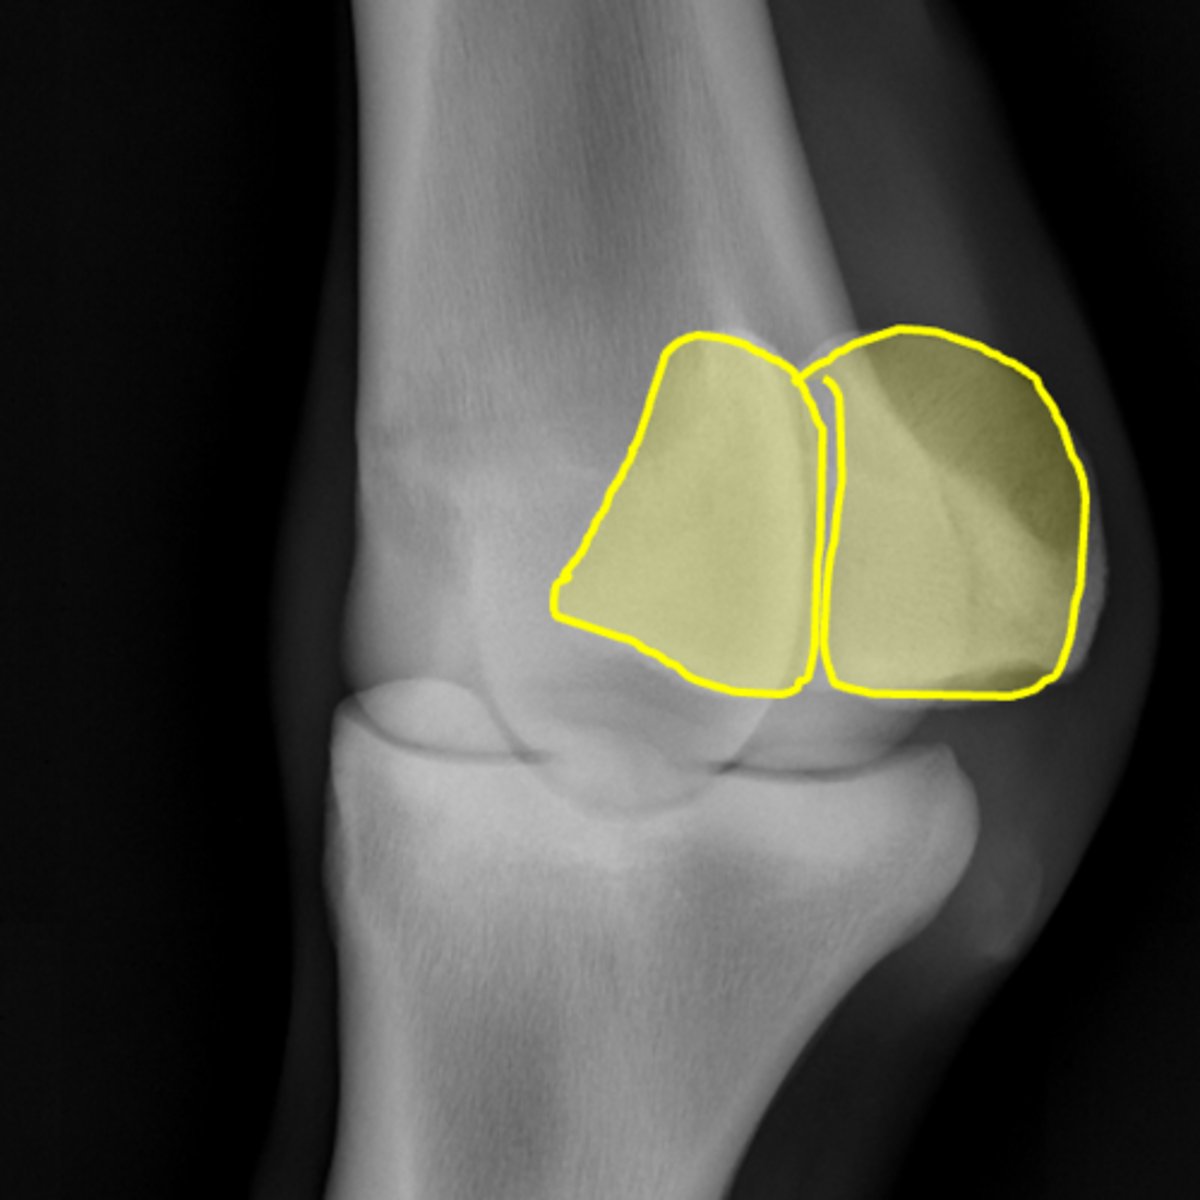

Fetlock joint, flexed LM

ID joint and view